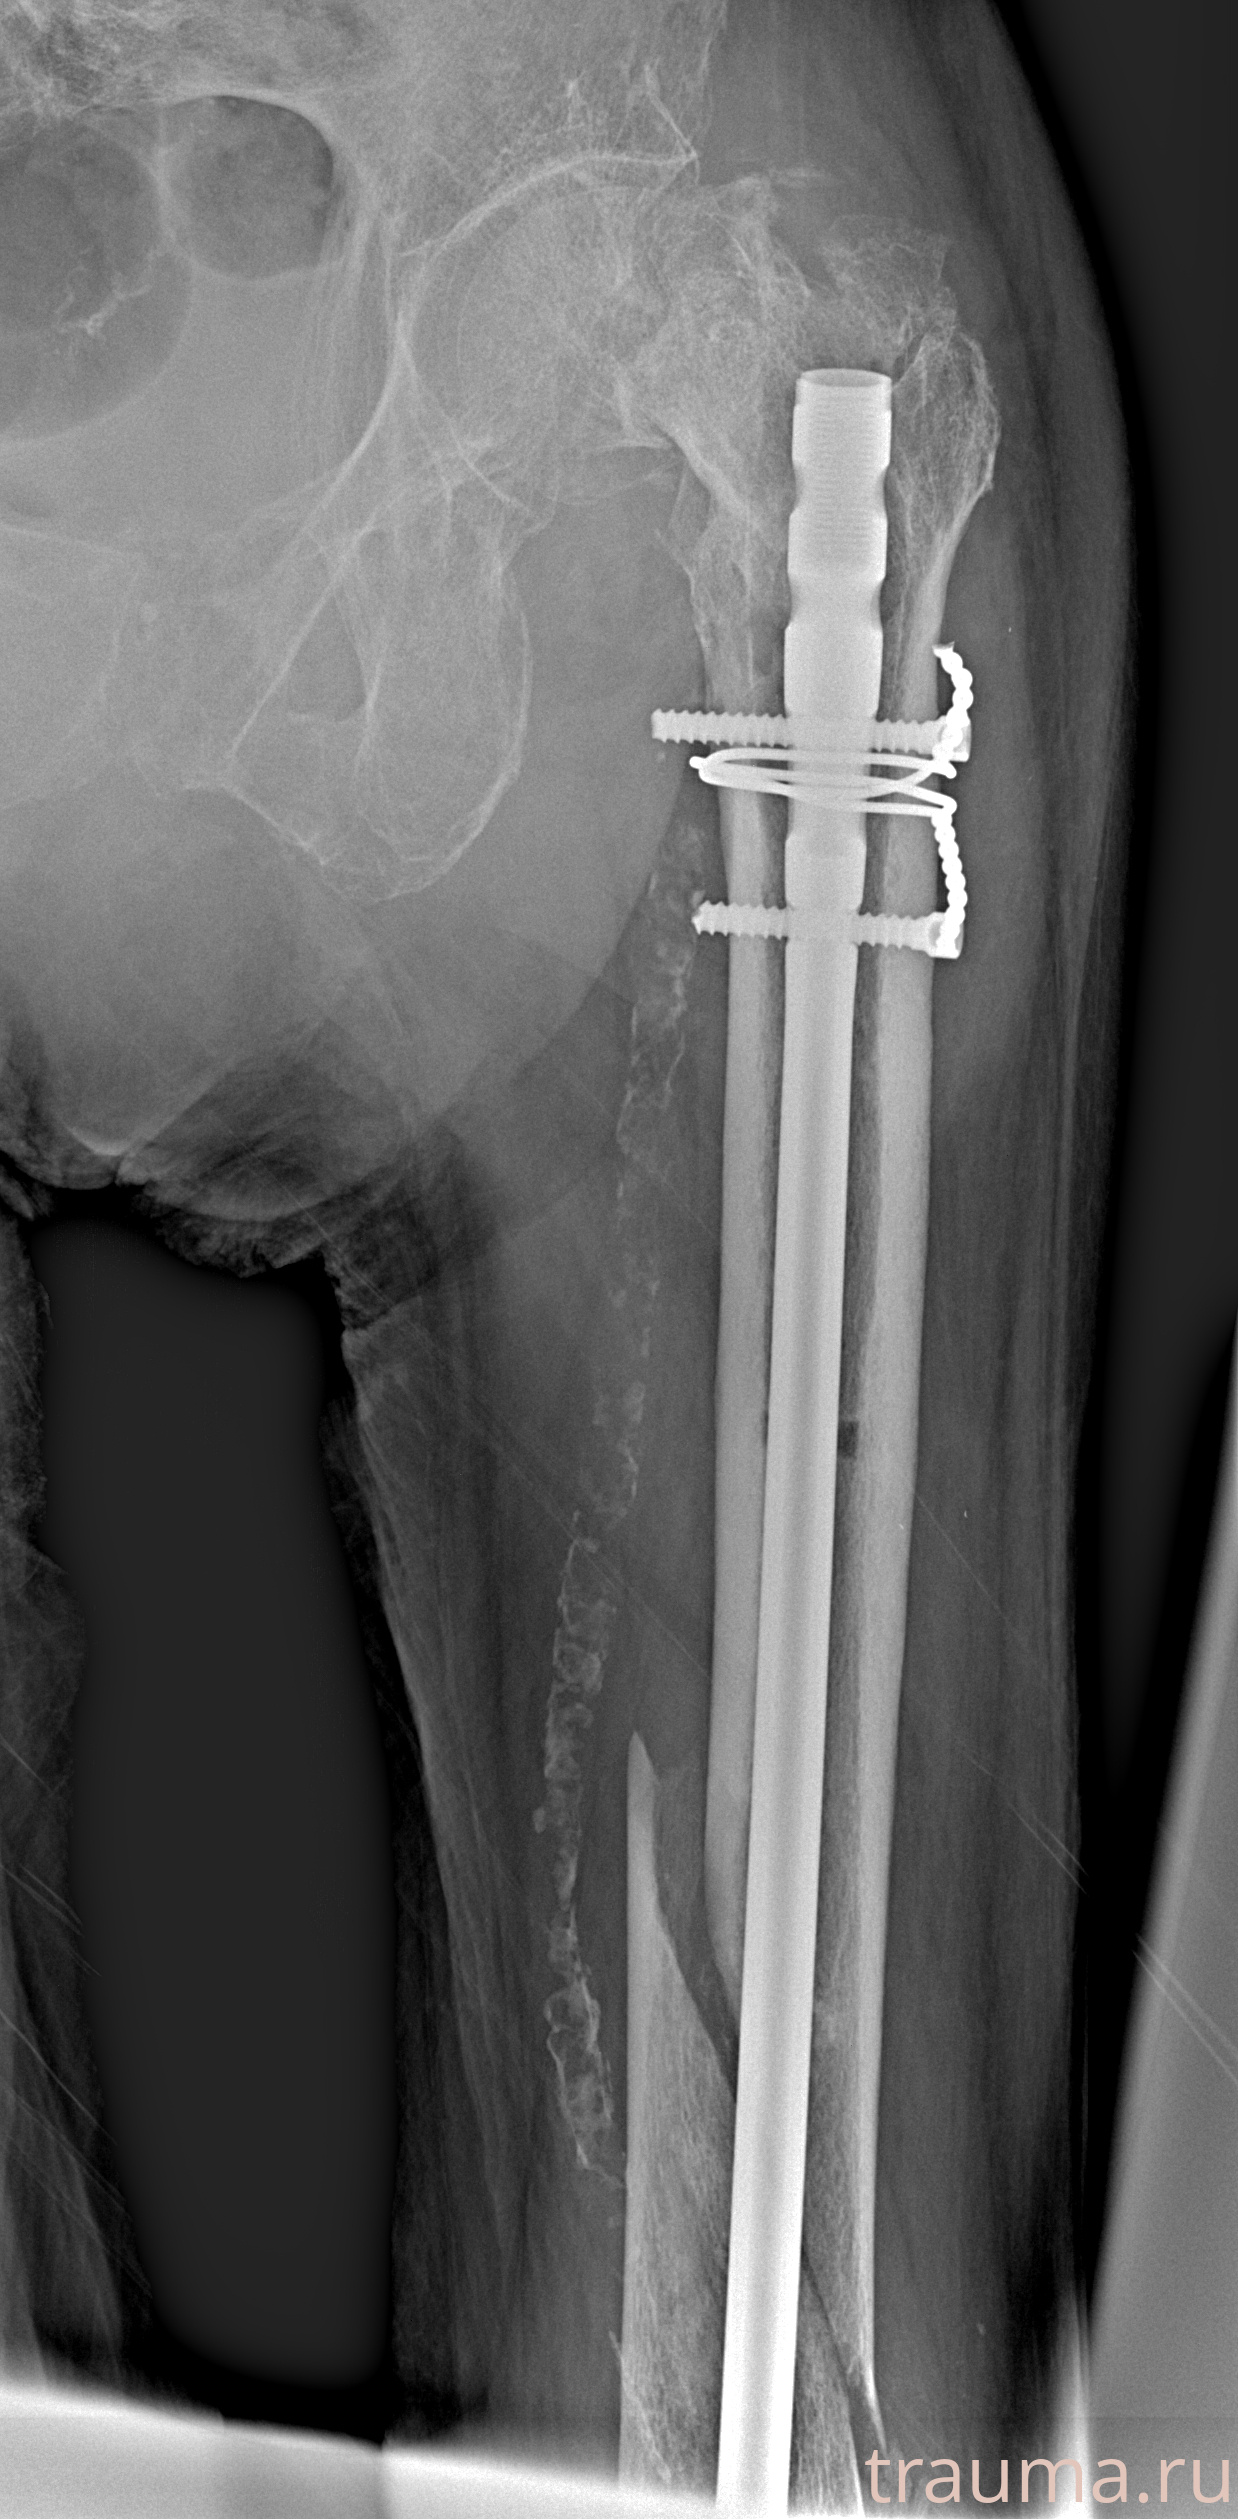

Рентгенограммы